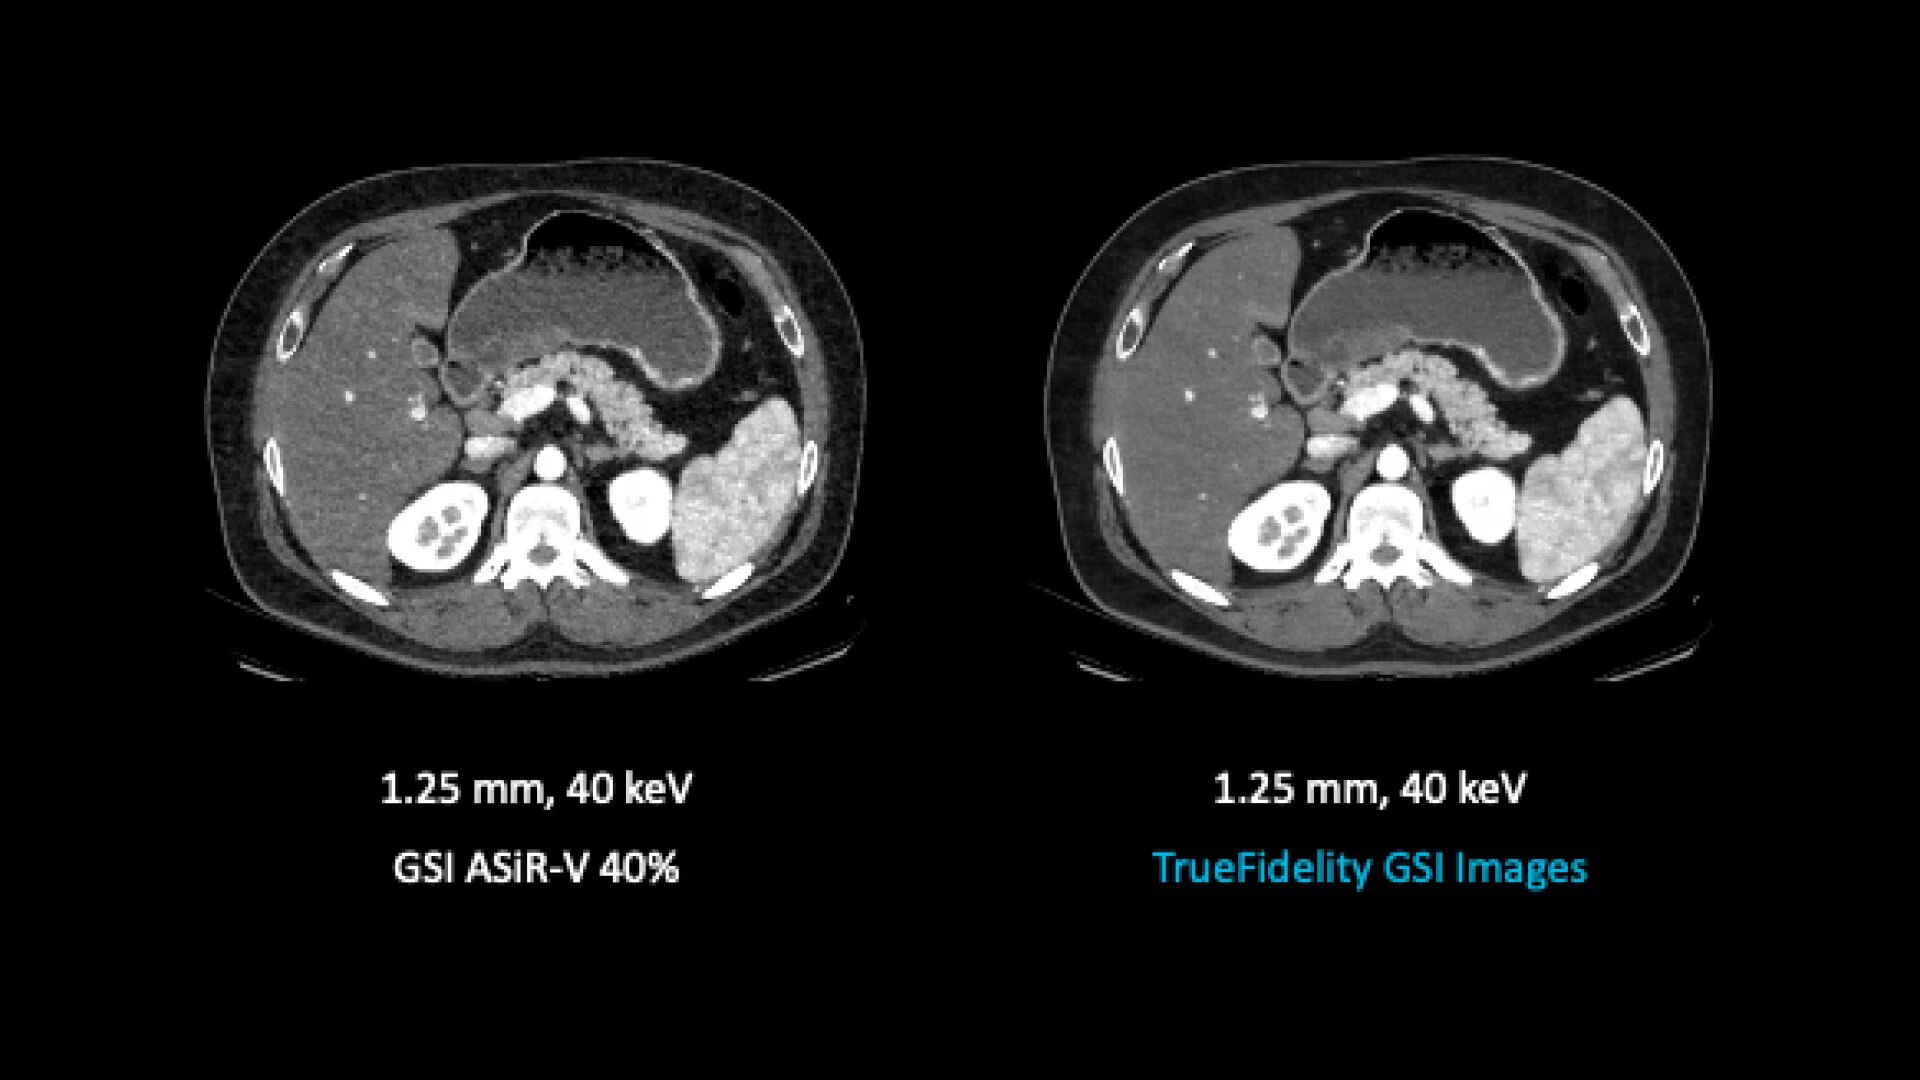

TrueFidelity for GSI now brings the potential to substantially reduce the image noise in all spectral image types

From virtual monochromatic images to material image pairs and virtual non-contrast images, with and without metal artifact reduction. Specifically, reducing the image noise inherent with low keV images resolves one of the traditional technical challenges in adopting more dual-energy protocols across the full patient population.